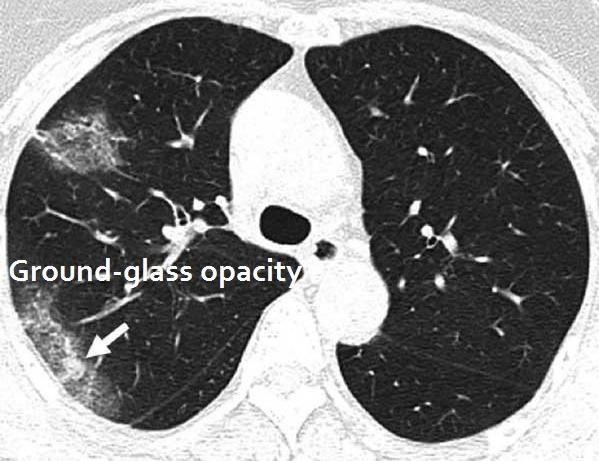

در علم پزشکی به این لکهها، کدورت شیشه مات (Ground-glass opacity) گفته میشود. فردی که به این ویروس مبتلا نباشد، رنگ ریههایش در سی تی اسکن کاملا سیاه است

لکههای به وجود آمده در نتیجه آزمایش سی تی اسکن بیمار مبتلا به کرونا نشان دهنده ایجاد مایع در ریههای فرد و درگیری آنها با ویروس است. حال میزان درگیری ریهها به تشخیص پزشک معالج فرد مبتلا اعلائم میشود.